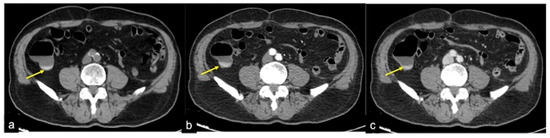

| Diverticulosis (Figure 33) | Asymptomatic or bleeding. | Protruding sacs where the vessels pass through the muscularis layer, between the mesenteric and antimesenteric taenia. |

| Angiodysplasia (Figure 5 and Figure 34) | Asymptomatic or bleeding. | Small hyperdense nodules within the intestinal wall, best defined in the portal phase of the study. |